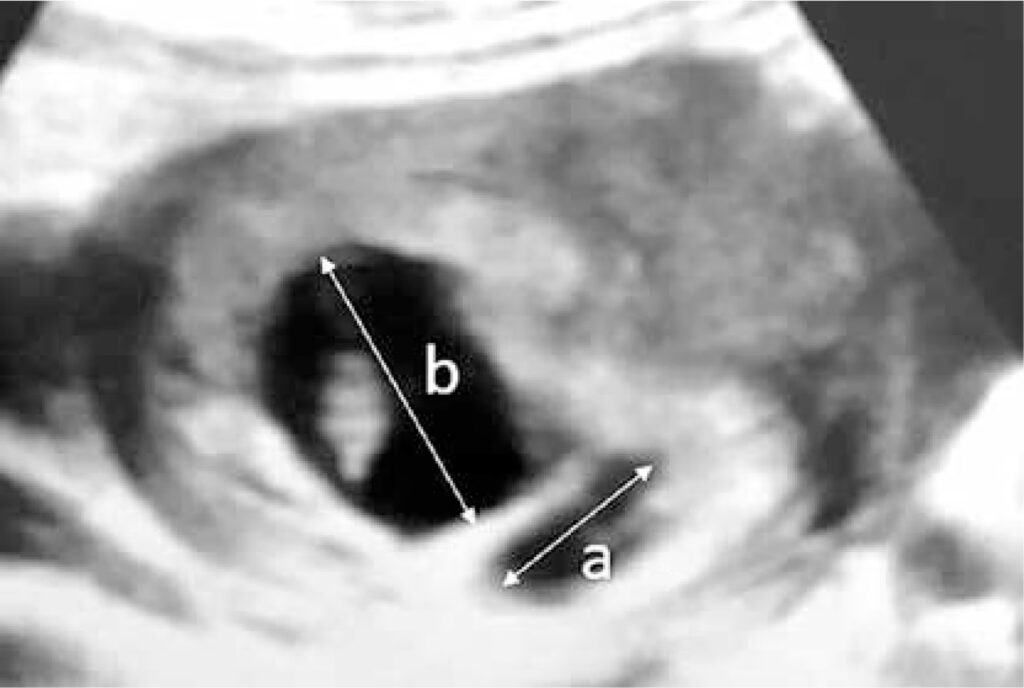

Ved scanningen kan sonografen se efter en halvmåneformet, mørk (hypoekkoisk eller anekkoisk) ansamling af væske mellem fosterhinderne og livmodervæggen. Nogle gange kan det være udfordrende at identificere, da udseendet kan variere. Et friskt hæmatom kan se anderledes ud end et ældre, og det kan forveksles med andre strukturer i livmoderen.